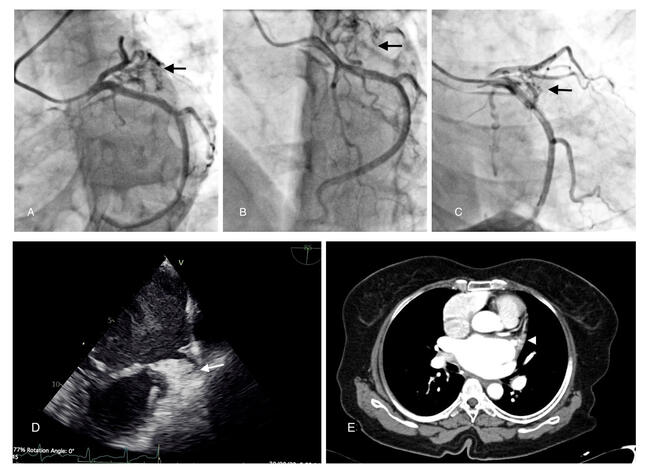

The left coronary angiogram taken in the left anterior oblique (LAO) caudal (Figure, A), LAO cranial (Figure, B), and right anterior oblique (RAO) caudal (Figure, C; Videos 1-3) projections showed small arterial channels arising from the left circumflex and terminating in an irregular collection of contrast medium (black arrows) in the region of the left atrial appendage (LAA). A transesophageal echocardiogram (TEE) (Figure, D [white arrow]) and computed tomography (Figure, E [white arrowhead]) then confirmed an organized clot in the LAA.

LAA clots frequently present with neovascularity and coronary-left atrial fistula. Feeder channels frequently arise from the left circumflex artery but may also arise from the right coronary artery.1 One of the differentials for this angiographic finding is LA myxoma.2,3 Myxoma, however, has a characteristic pattern: the “sea anemone” appearance (a central basal vascular network giving rise to a vascular stem that diverges into smaller vessels). Delayed enhancement and clearance of contrast in myxomas may also help differentiate it from the LAA clot.